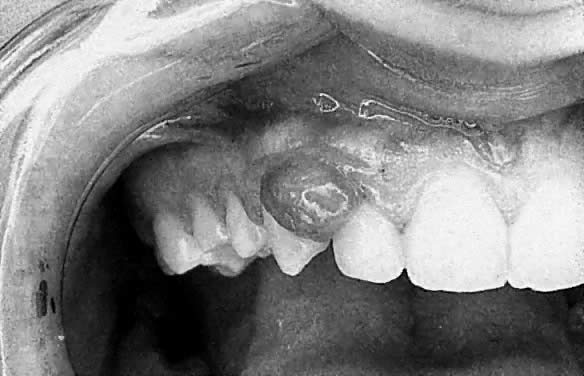

Apart from these generalized gingival changes, pregnancy may also give rise to the formation of tumor-like growths (epulides), along the gingival margin (Fig. 2). A number of terms for this lesion have been suggested, such as pregnancy tumor, epulis gravidarum, and pregnancy granuloma. Of these, pregnancy granuloma is preferred, because the histologic structure is similar to the structure in pyogenic (telangiectatic) granuloma.25 The reported frequency of pregnancy granulomas varies from 0% to 9.6%.26,27 The granuloma occurs more frequently in the maxilla, favoring the vestibular aspect of the anterior region.

Fig. 2. Pregnancy granuloma in a 27-year-old patient during the fifth month of pregnancy.

There appears to be no correlation between the appearance of this lesion and the month of pregnancy, although patients may notice the lesion more often in the second or third trimester, owing to its growth or the complications of its vascular nature.28 The lesion often shows rapid growth, although it seldom becomes larger than approximately 2 cm in diameter. A pregnancy granuloma is generally a pedunculated, soft growth of interdental origin; is fiery red; and often has small, fibrin-covered areas (see Fig. 2). Pregnancy granulomas frequently bleed readily when touched and have a tendency to recur rapidly.